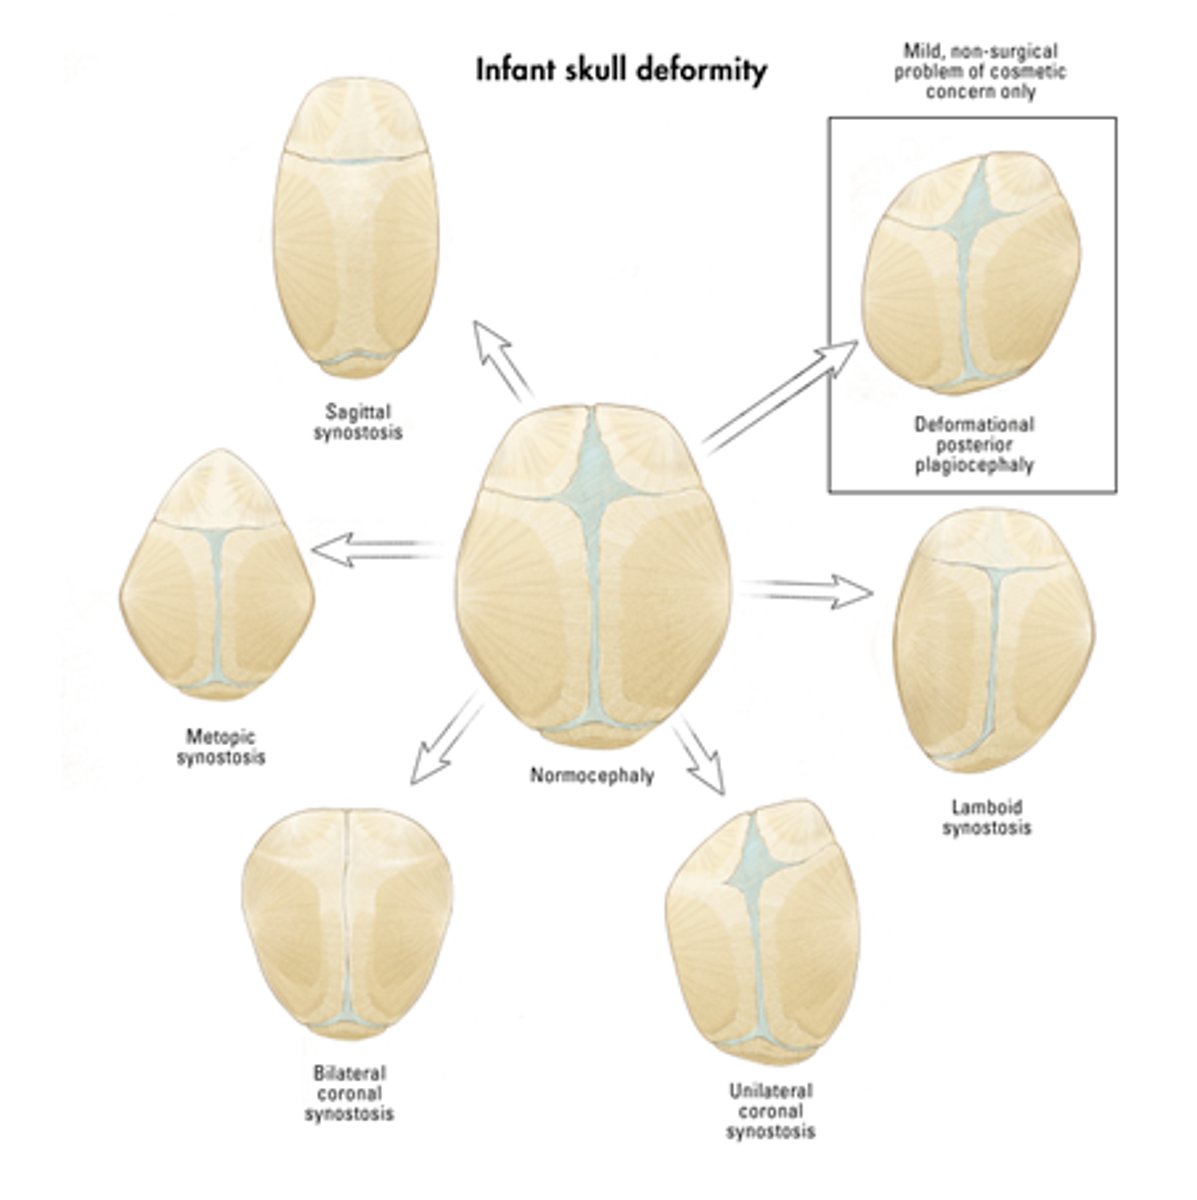

What is craniosynostosis and how is it corrected?

the premature ossification of 1 or more sutures resulting in bulging at the fontanelle at the contralateral side. Treated by helmets and or surgery

metopic craniosynostosis

fusion of the frontal suture resulting in elongation at the forehead

Sagittal Craniosynostosis

premature closure of sagittal suture resulting in posterior elongation

unicoronal craniosynostosis

one-sided closure of the coronal suture resulting in bulging at the contralateral forehead

lambdoid craniosynostosis

closing of one side of the lambdoid suture resulting in posterior bulging at the contralateral side